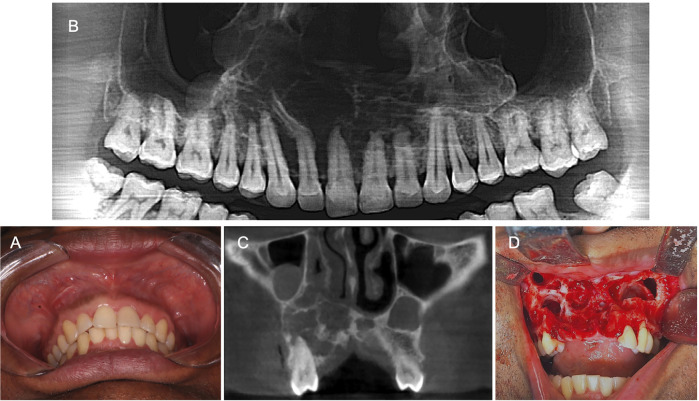

Background: Glandular Odontogenic Cyst (GOC) is a rare benign lesion with unique histological features, and more aggressive growth pattern compared to other odontogenic cysts. GOC typically presents as an asymptomatic, slow-growing swelling, predominantly affecting middle-aged males and often localized in the anterior mandible. This report details three cases of GOC affecting the maxilla.

Case report: Case 1 presented a GOC mimicking a residual cyst in the maxilla. Case 2 involved a GOC located within the maxillary sinus. Case 3 showed a multilocular radiolucent GOC in the anterior maxilla. All cases were treated by surgery, and the diagnosis was confirmed through microscopic examination.